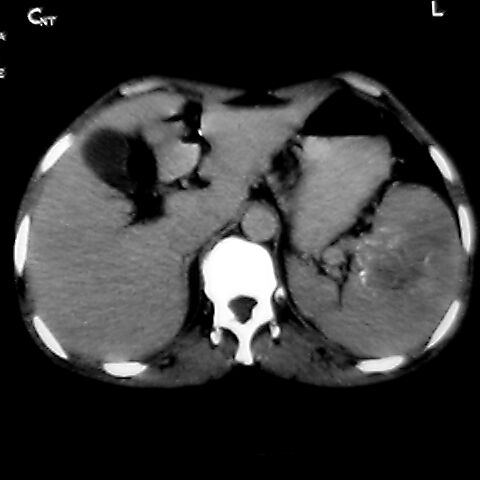

女 48岁 食道癌术前体检发现脾占位。

考虑脾脏血管瘤,中央低密度为血栓形成

脾脏低密度灶伴钙化,增强化明显,中心见液化坏死灶,强化延时明显。考虑血管瘤。转移瘤待排。

1,脾血管瘤。2,右肝,右肾小囊肿。